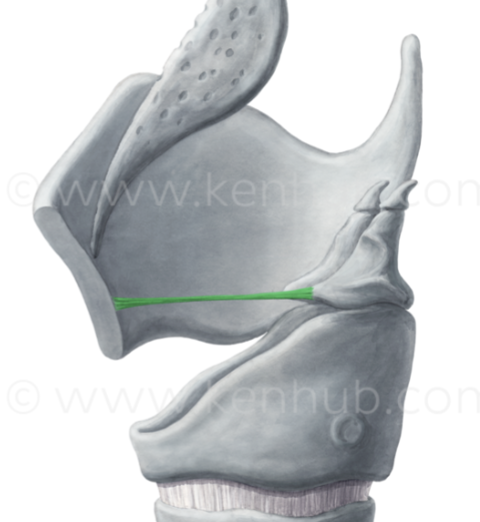

What ligament is this?

Conus elasticus

What ligament is this?

Vocal ligament

What ligament is this?

Posterior cricoarytenoid ligament